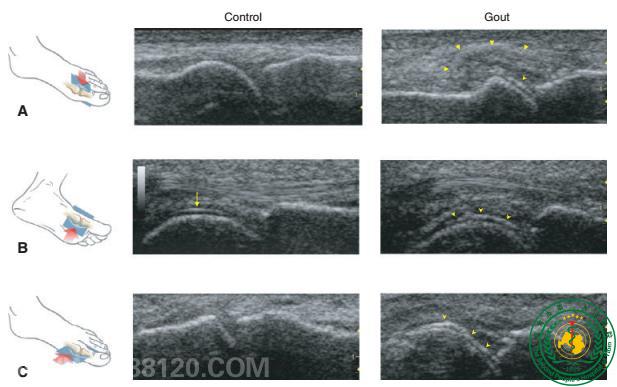

有,近年的研究发现超声在痛风患者中能较敏感发现尿酸盐的沉积征象,当超声检查关节有双轨征时,可有效辅助诊断痛风;何谓“双轨征”?是指单钠尿酸盐结晶在超声下表现为高强回声,沉积并广泛覆盖于软骨表面,使得低回声的软骨表面回声增强,与深处的骨性关节面强回声线形成双轨征。多研究表明有症状的痛风患者关节双轨征检出率较高,以第一跖趾最多见。

全民关注痛风日,我们在行动

我科自开展肌骨超声以来,已为数百名关节炎(痛)患者明确原因,得以得以及时治疗。